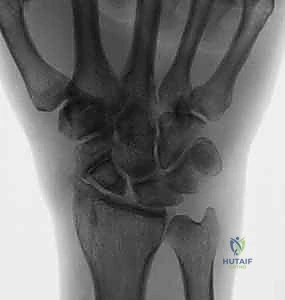

متلازمة SNAC (Scaphoid Nonunion Advanced Collapse) هي حالة تدهور تدريجي ومأساوي لمفصل الرسغ. تبدأ القصة بكسر في العظم الزورقي (غالباً بسبب السقوط على يد ممدودة). إذا لم يتم تشخيص هذا الكسر أو لم يلتئم بشكل صحيح، فإن العظم الزورقي ينقسم إلى قطعتين تتحركان بشكل غير طبيعي ومستقل عن بعضهما البعض.

هذه الحركة غير الطبيعية تخلق احتكاكاً مستمراً (Micro-trauma) مع العظام المجاورة، وتحديداً عظم الكعبرة (Radius). بمرور الوقت (أشهر أو سنوات)، يؤدي هذا الاحتكاك إلى تآكل الغضاريف الناعمة التي تغطي العظام، مما يسبب خشونة مفصلية شديدة (Osteoarthritis).

مراحل تطور متلازمة SNAC:

- المرحلة الأولى (Stage I): خشونة وتآكل في المفصل بين القطب البعيد للعظم الزورقي وعظم الكعبرة (الناتئ الإبري الكعبري).

- المرحلة الثانية (Stage II): يمتد التآكل والخشونة ليشمل المفصل الزورقي الكبير (Scaphocapitate joint).